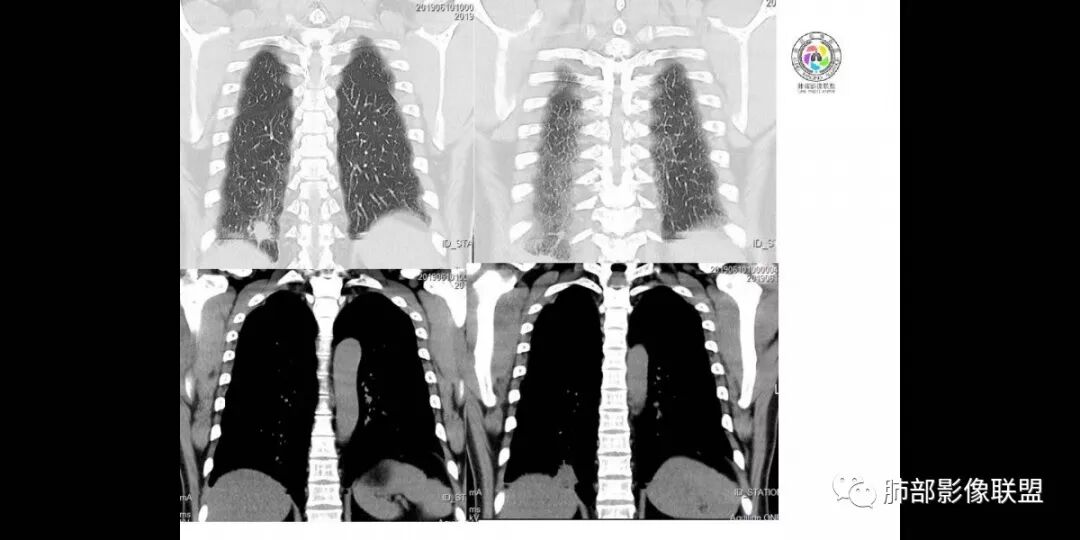

患者男,45岁,因乏力、低热、心悸入院,最高体温38℃,偶有咳嗽、无咳痰、咯血,肿瘤标志物阴性。

影像资料

中年男性,乏力  低热入院,胸CT:右肺下叶后基底段结节样病变,病灶周围可见细支气管扩张,病灶边缘可见短软毛刺,病灶周围有毛玻璃影,冠状位肺窗病灶与膈胸膜呈宽基地,纵隔窗可见病灶内空洞及低密度区,增强明显强化及延迟强化,考虑良性感染性病变,隐球菌肺炎?,结核?。但在冠状位肺窗有一支细支气管在病灶旁有截断,还得除外肺癌的可能性。

中年男性,乏力,低热,右肺下叶后基底段近膈肌缘小团块样病灶,边缘平直,部分内凹,周围磨玻璃,边缘模糊不清,周围少许毛刺,柔软,增强后明显渐进性强化,其内可见少许低密度区,边界清晰,考虑感染性病变,op合并坏死可能。

右下叶病灶,周围ggo边界清,轴位病灶似乎有收缩,平直征,但是冠状重建可以看看病灶边缘膨隆,强化不均匀,持续强化,结合病史首先考虑肺癌,腺癌可能性大,鉴别隐球,op。

患者中年男性,以乏力、低热、心悸入院。胸部CT:右肺下叶后基底段近胸膜实性结节灶,病灶周围磨玻璃模糊影,可见短毛刺,边缘呈刀切、平直,冠状位肺窗病灶与膈胸膜呈宽基地,纵隔窗可见病灶内空洞及低密度区,增强明显强化及延迟强化,综合考虑良性感染性病变。肺隐球菌病可能大,机化性肺炎、腺癌次之,结核待排。

右肺下叶后基底段结节,边缘较清,有浅分叶,病灶长轴与胸膜平形,以平直收缩为主,局部稍膨隆,有长短不一的毛刺,边缘模糊,周围有小片状模糊hggo,中心有小空泡或小空 洞,内壁光整,增强后延迟强化,提示会不会有纤维组织成份,而且空腔内壁强化明显且完整,邻近胸膜有糊墙,考虑炎性病变,机化性肺炎合并脓肿?鉴别癌。

增强特点:多为明显强化,CT值增加40-80HU之间),一般很少出现深分叶、钙化及淋巴结肿大的特点,常可与周围性肺癌鉴别。